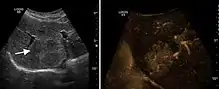

Benign focal nodular hyperplasia (CEUS). Gray scale examination (left) detects the lesion. CEUS examination (right) allows characterization of tumor nature based on central contrast enhancement and centrifugal dispersion.

It is a tumor developed secondary to a circulatory abnormality with abundant arterial vessels having a characteristic location in the center of the tumor, within a fibrotic scar. A radial vessels network develops from this level with peripheral orientation. The tumor's circulatory bed is rich in microcirculatory and portal venous elements. The incidence is higher in younger women and tumor development is accelerated by oral contraceptives intake. 2D ultrasound appearance is a fairly well-defined mass, with variable sizes, usually single, solid consistency with inhomogeneous structure. Rarely the central scar can be distinguished. Spectral Doppler examination detects central arterial vessels and CFM exploration reveals their radial position. CEUS examination shows central tumor filling of the circulatory bed during arterial phase and completely enhancement during portal venous phase. During this phase the center of the lesion becomes hypoechoic, enhancing the tumor scar. During the late phase the tumor remains isoechoic to the liver, which strengthens the diagnosis of benign lesion.

Encephaloid hepatocellular carcinoma (CEUS). Contrast tumor enhancement is observed on the left during arterial phase. The “wash-out” phenomenon can be seen on the right, during portal venous phase.

HCC appearance on 2D ultrasound is that of a solid tumor, with imprecise delineation, with heterogeneous structure, uni- or multilocular (encephaloid form). An "infiltrative" type is also described which is difficult to discriminate from liver nodular reconstruction in cirrhosis. Typically HCC invades liver vessels, primarily the portal veins but also the hepatic veins . Doppler examination detects a high speed arterial flow and low impedance index (correlated with described changes in tumor angiogenesis). The spatial distribution of the vessels is irregular, disordered. CEUS examination shows hyperenhancement of the lesion during the arterial phase. During the portal venous phase there is a specific "wash out" of ultrasound contrast agent (UCA) and the tumor appears hypoechoic during the late phase. Poorly differentiated tumors may have a stronger wash out leading to an isoechoic appearance to the liver parenchyma during portal venous phase. This appearance was found in approx. 30% of cases. The described changes have diagnostic value in liver nodules larger than 2 cm.